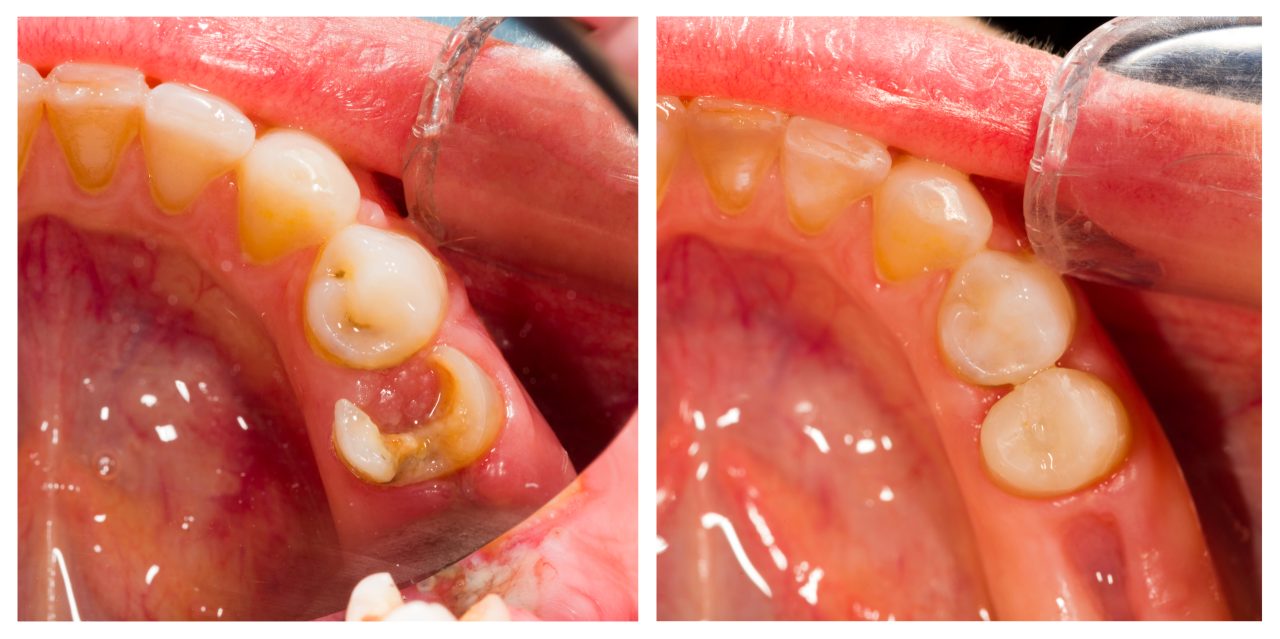

O capeamento pulpar direto é indicado quando há uma exposição direta da polpa dentária, seja de origem mecânica, traumática ou cariosa (desde que minimamente contaminada).

O capeamento indireto, por sua vez, é realizado quando há uma cárie profunda, mas sem exposição da polpa.

A ideia é remover seletivamente a dentina infectada e preservar a dentina afetada, minimizando o risco de exposição e estimulando a remineralização ou a formação de dentina terciária.

Após o isolamento absoluto do campo operatório, realiza-se a remoção cuidadosa da lesão cariosa ou do tecido fraturado até a exposição pulpar.

Após o isolamento absoluto, remove-se a dentina cariada superficial com brocas ou instrumentos manuais, deixando-se uma camada de dentina mais próxima da polpa que, embora afetada, pode ser remineralizada.